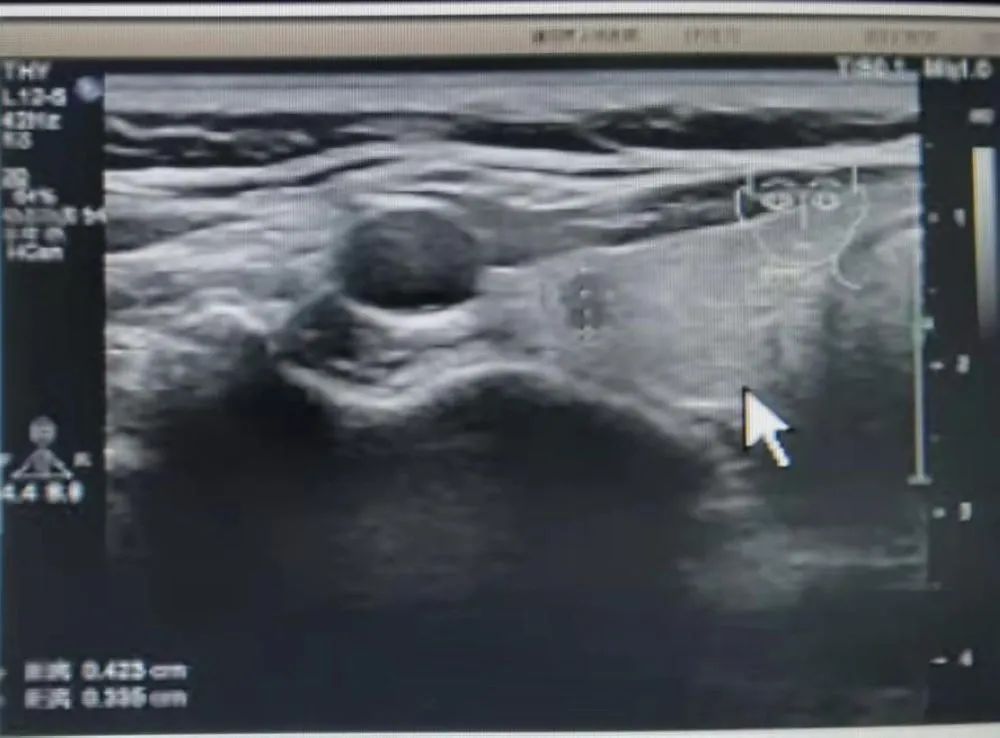

患者冯某某,女,21岁,大三在读,在我院超声科进行颈部超声检查后,发现右侧叶甲状腺类结节,并且经过活检穿刺病理为不能除外甲状腺乳头状癌,这如同一个晴天霹雳般的坏消息,让患者难以接受,如花绽放般的年龄,却要面对如此残酷的抉择。如果选择手术切除,术后颈部的瘢痕、终身服药的不便成为了现实难题,让冯某某难以接受传统手术疗法。在了解到她的困扰后,我院甲状腺乳腺外科迅速启动科内会诊及病例讨论机制,决定采用超声引导下的射频消融治疗,对冯某某的恶性结节进行局部灭活,并且尽可能保留正常腺体。

通过术前评估,细致准备,在实时超声的引导下,射频消融针精准地进入恶性病灶内,仅用时3分钟左右,消融范围就完全覆盖病灶并局部扩大消融范围。